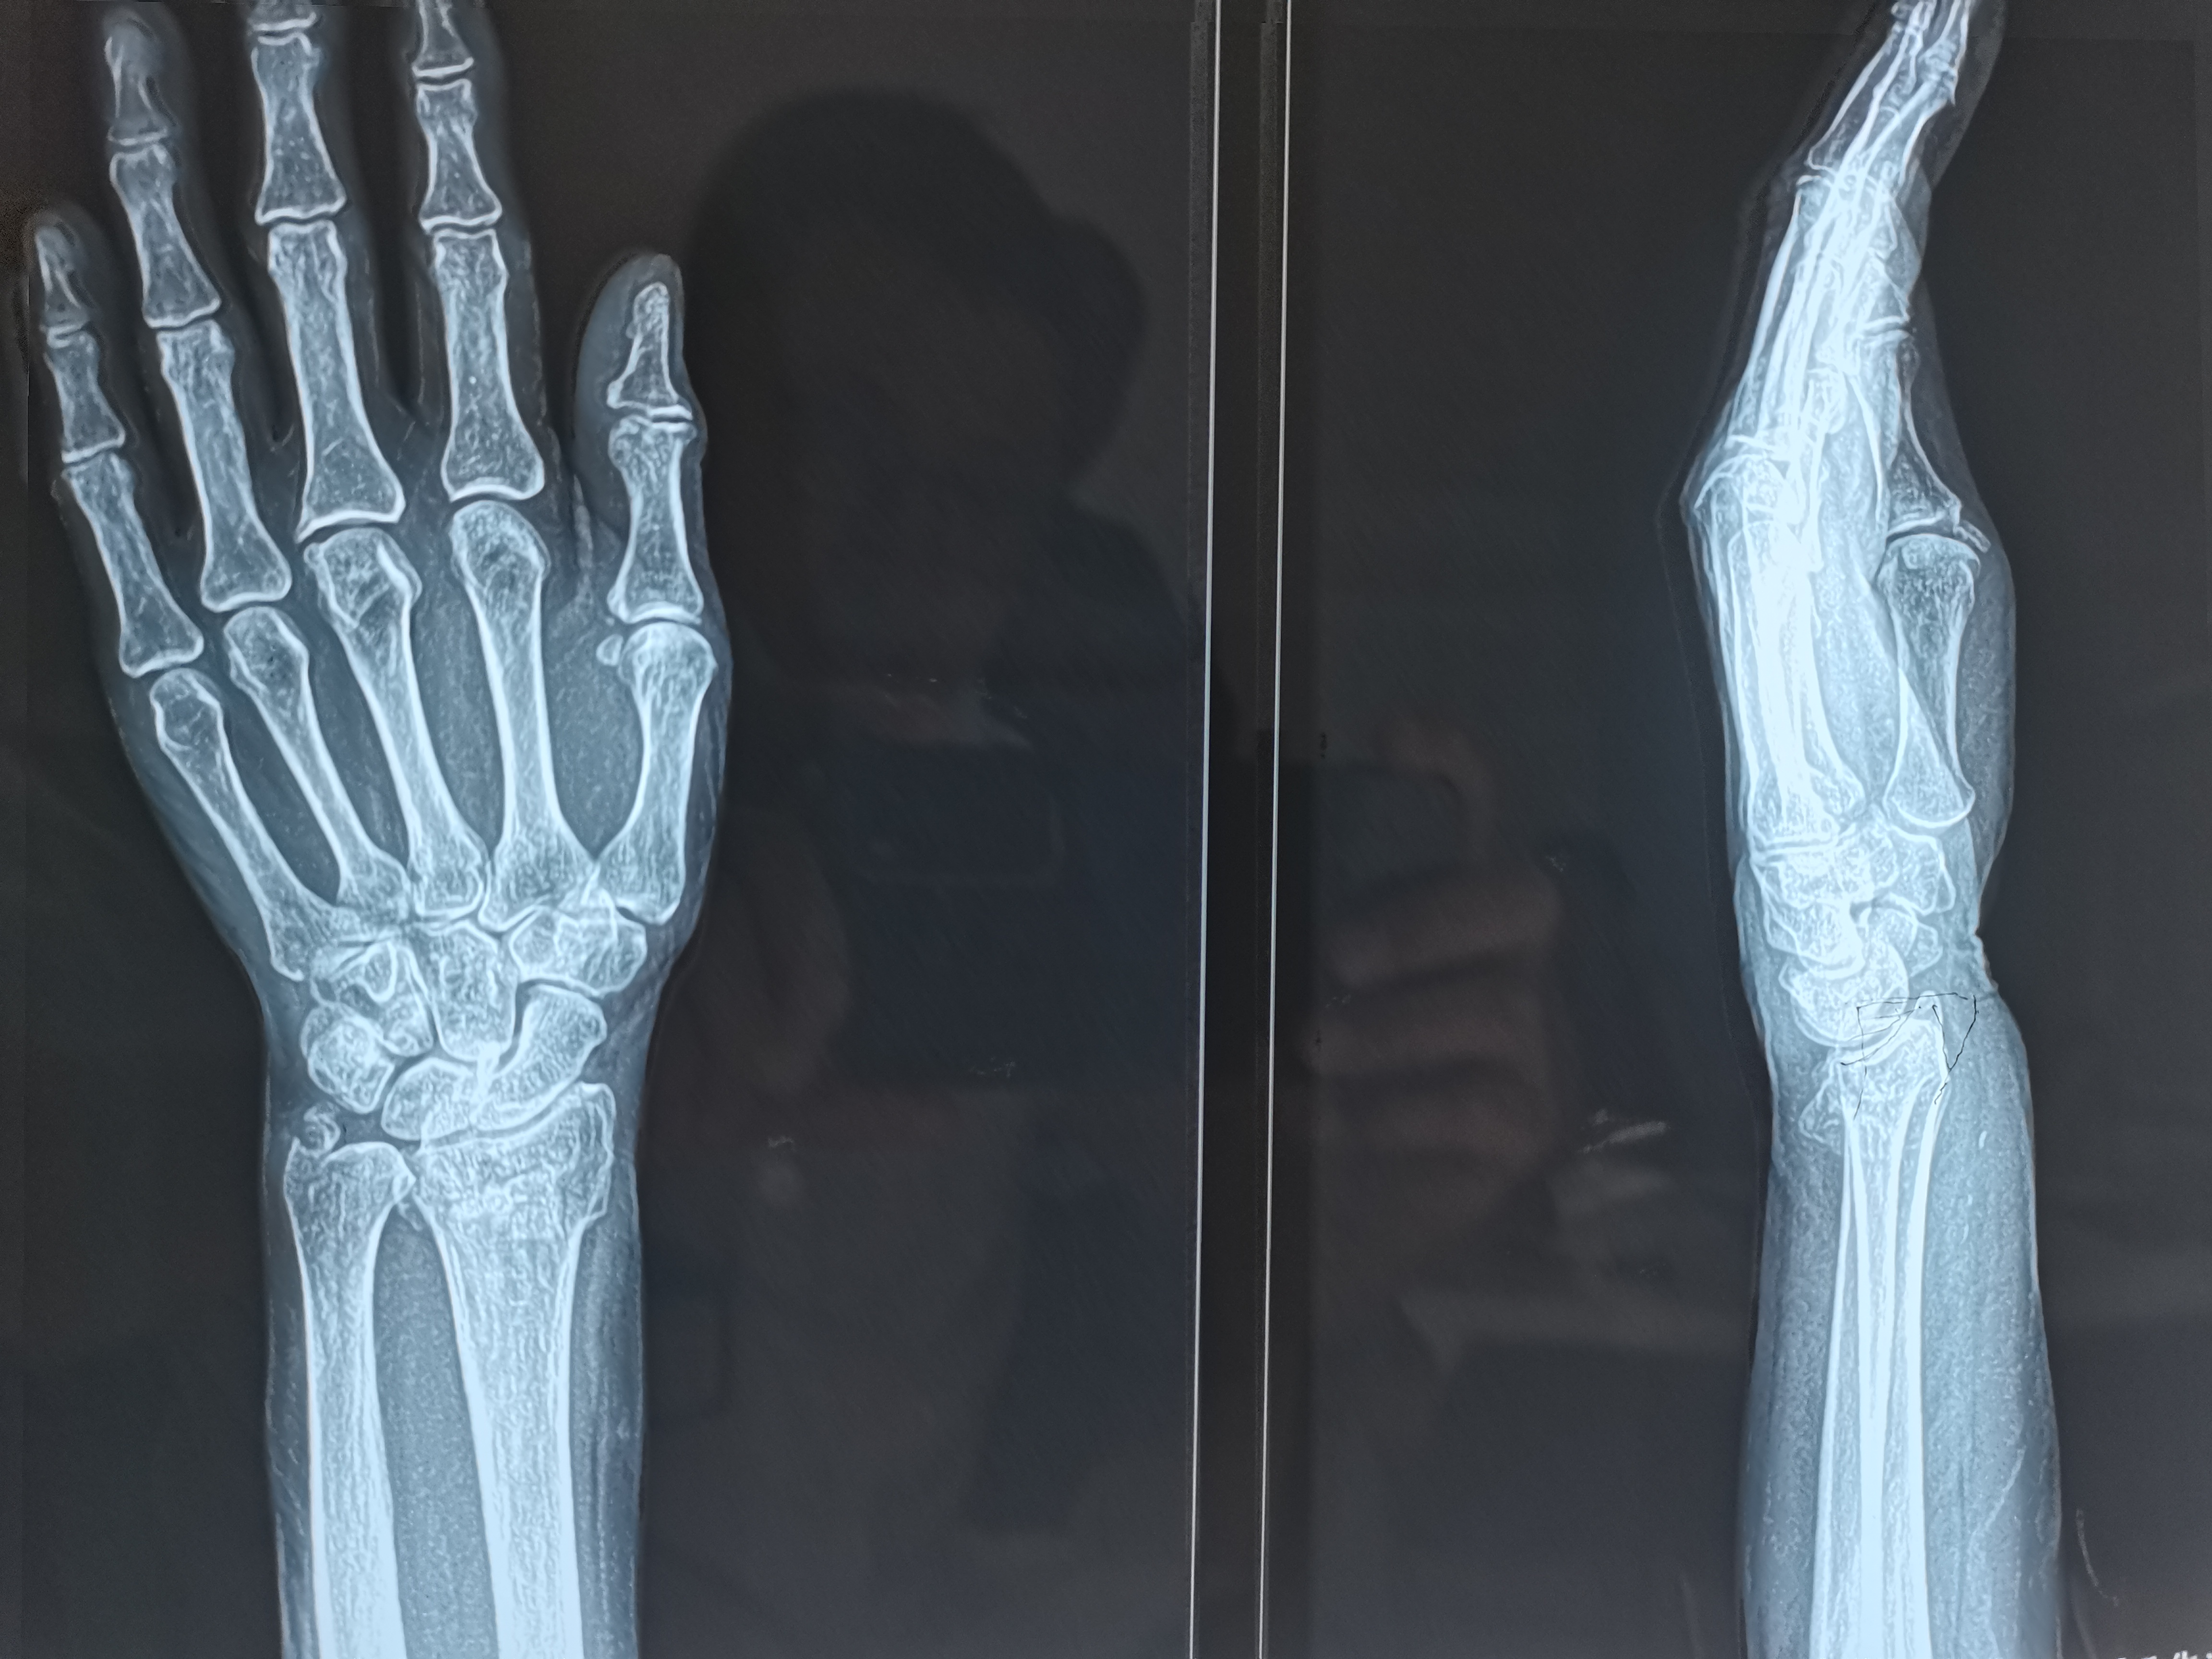

1. 评估病情:通过X线片明确骨折类型(如Colles骨折、Smith骨折、Barton骨折)、移位方向(掌侧/背侧移位、桡侧偏移、短缩等),同时检查腕部神经(正中神经为主)、血管功能。

1. 影像学检查:复位后即刻复查X线片,确认骨折对位对线良好,若仍有移位需再次复位。

手法复位的成功与否取决于对骨折移位规律的掌握和操作技巧的熟练度,复位后定期复查X线片(复位后即刻、1周、2周、4周)至关重要。多数患者通过规范的手法复位和后续康复,可恢复良好的腕关节功能。